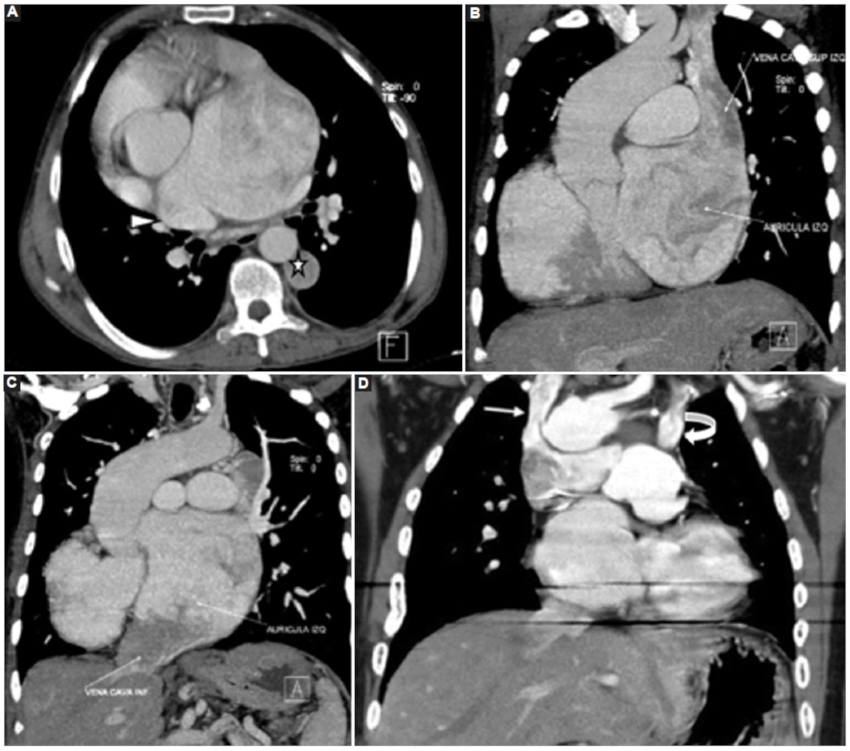

El retorno venoso pulmonar y sistémico puede ser anómalo y tiene una gran variedad de presentaciones. En el caso 1 se observó una anomalía parcial del retorno venoso pulmonar, la vena pulmonar superior derecha drenando a la aurícula derecha (Fig. 8A), asociado a un retorno venoso sistémico anómalo con la vena cava superior e inferior drenando ambas a la aurícula izquierda y estableciendo así un shunt pulmonar del retorno sistémico (Fig. 8 B y C). En el caso 3 se observaron dos venas cava superiores (derecha e izquierda); que drenan a sus respectivas arterias pulmonares (Fig. 8 D) determinando una alteración del retorno venoso sistémico.